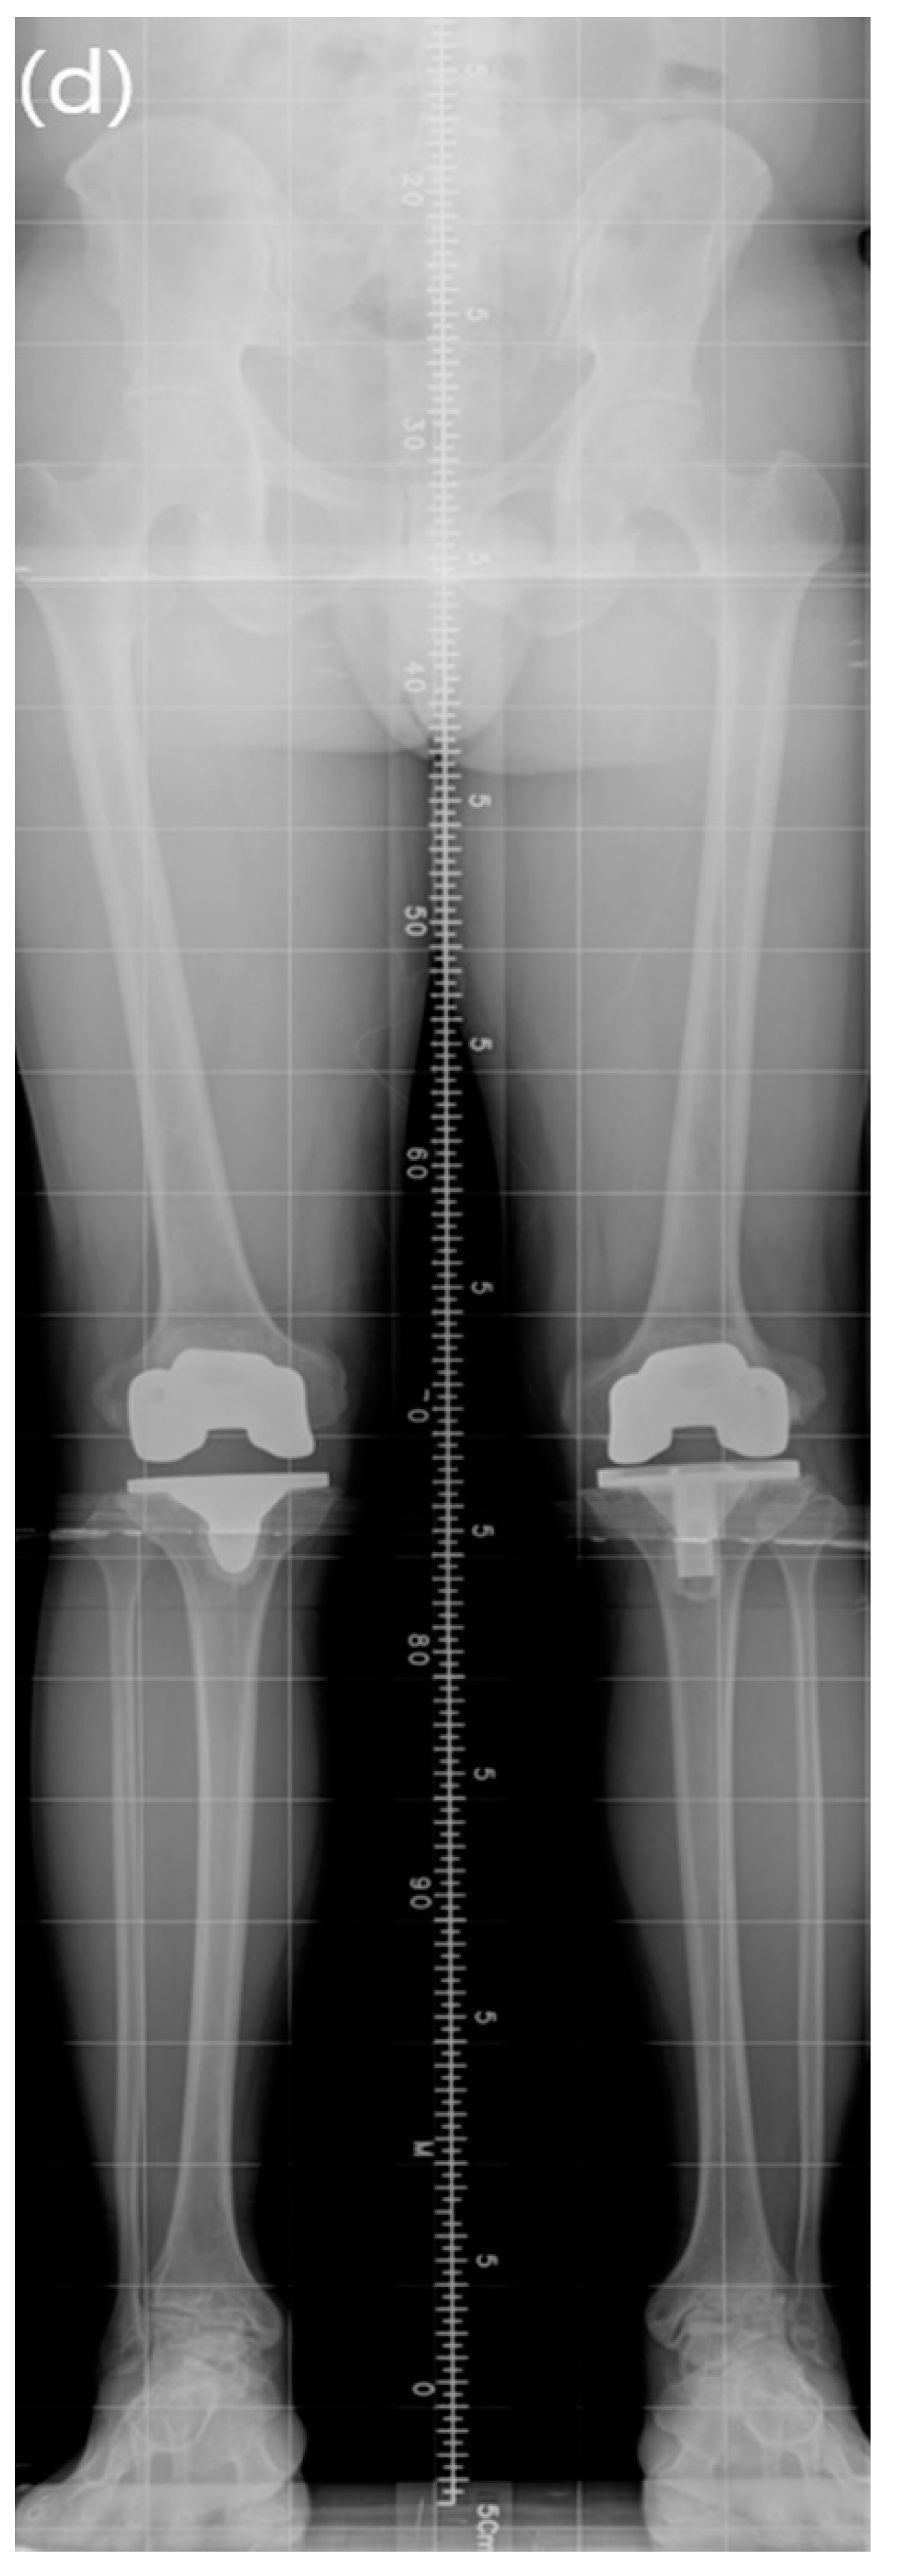

| Lower limb alignment | |||

| Varus knee (n = 33) (°) | −6.92 ± 3.71 (−0.7 to −16.6) | −0.90 ± 2.73 (−5.3 to 4.77) | <0.001 |

| Valgus knee (n = 45) (°) | 6.57 ± 5.20 (0.3 to 19.3) | 0.62 ± 2.47 (−2.52 to 4.35) | <0.001 |